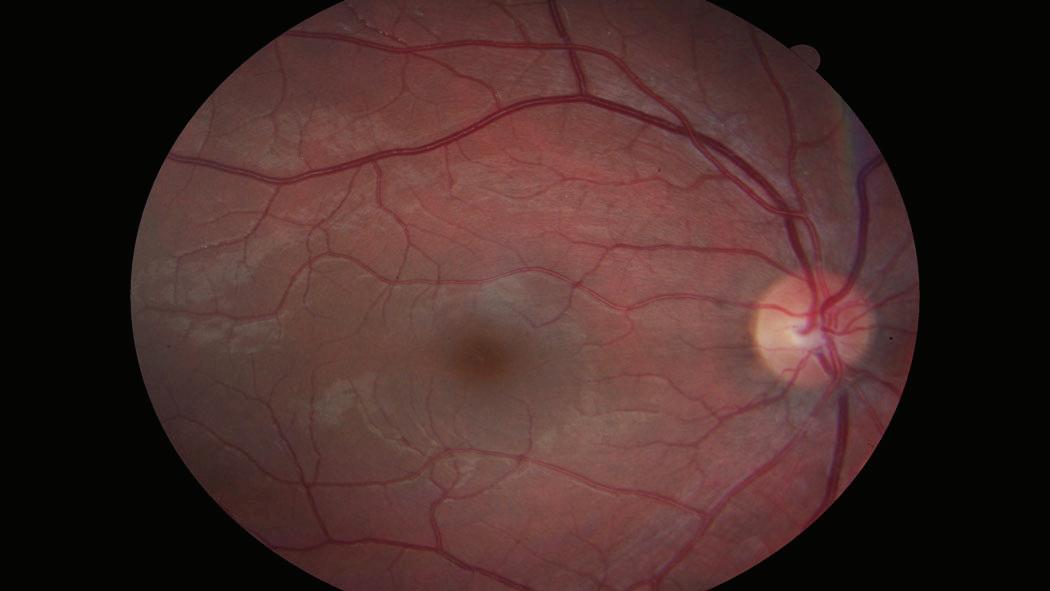

6 2 Inside the Eye Inside the Human Eye are parts that have a significant impact on how we receive visual information that the brain uses to “see”. It is important to understand these parts as well as recognize some of their limitations and capabilities.

• Macula - The small oval shaped and pigmented spot in the center of the retina where the structures are specialized for high acuity central vision. While peripheral vision loss may go unnoticed, if the macula is damaged loss of central vision will be immediate. In most cases this is caused by macular holes resulting from macular degeneration. However, an explosion or sharp blow could burst the blood vessels going to the macula and destroy it (i.e. IED blast, head trauma from a car crash, fall, punch, kick, or impact from a tool or weapon).

• Fovea Centralis - This is a small depression in the retina located in the center of the macula where visual acuity is it’s best. This is where the center of the Functional Field of View is focused on the densely packed Cone cells. The sharp central vision that we use to read comes from this portion of the eye.

• Functional Field of View - The actual area of light information that our eyes and brains actually perceive is measured angularly. It is different from person to person; but on average it is 6° for Males and 11° for Females.

6.3 Cones and Rods. As stated previously in the section, there are two types of cells in the retina of the eye. These photosensitive cells react to light energy received into the eye and transmit the signals to the optic nerve (also known as the second cranial nerve) which then sends these impulses to the brain.

• Cones - These are cells within the retina of the eye that are responsible for color vision. Cone cells function best with bright lighting conditions. There are three types of cone cells, each one being responsible for a different color or wavelength of light; red, green, and blue. The highest concentration of cone cells is in the macula where they are more densely packed in the fovea centralis.

• Rods - These are cells within the retina of the eye that are responsible for low light or night vision as well as our peripheral vision. There are more rod cells than cone cells and they are more spread out throughout the retina. Rod cells are also more sensitive and therefore can detect lower levels of light, however they cannot discern color.

Our rod cells also detect light, motion, and edges. For example, if someone throws a ball at you unexpectedly outside of your functional field of view the rod cells in your eye detects the movement causing the muscles in your eye to orient onto the ball where by your cone cells identify the physical location of the ball and you attempt to catch or block it.

6.4 Visual Limitations. Even though the human eye is very effective at receiving light information at amazing speeds, it does have some limitations. There are certain physiological conditions that prevent the eye from collecting visual information and transmitting it to the brain. These physiological limitations are known as blind spots and aberrations.

HTMBPR Figure 6.2 The human eye has many internal parts that make it capable of sensing amazing amounts of light information. However, there are limitations such as bind spots, aberrations, and visual/perceptual fill.

• Blind Spots - This is a phenomenon this occurs because of the optic nerve bundle. In the retina of the eye the optic disk is where all of the nerves connect to the optic nerve. Because of this there are no photoreceptors in this area (cones and rods) and therefore the light image that impacts that part of the eye does not register, causing a blind spot. Because the brain has to form a complete picture it will fill this blind spot in with the surrounding information.